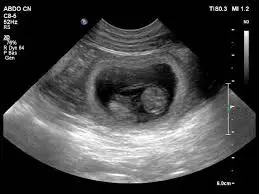

Echographie